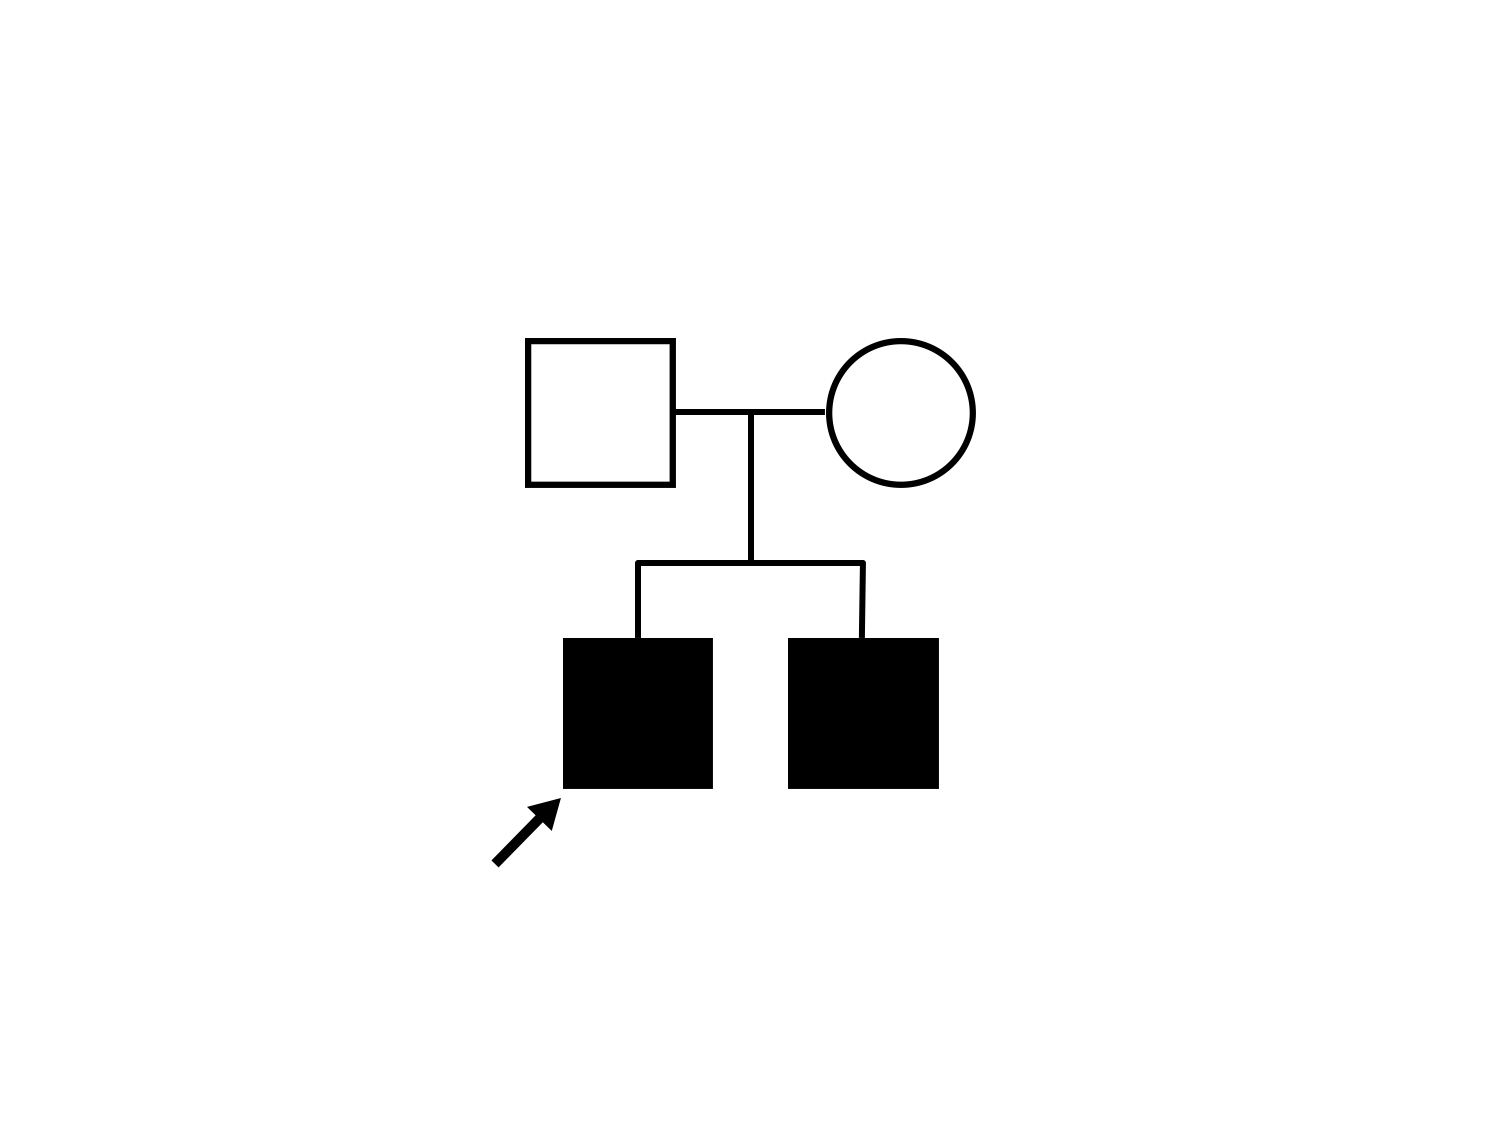

AR Stargardt Disease (IIA)

AR Stargardt Disease (IIA)

Diagnosis & molecular findings

| Disease | Gene | Allele 1 variant(s) | Allele 2 variant(s) | Inheritance mode |

|---|---|---|---|---|

| AR Stargardt Disease | ABCA4 | Leu541Pro CTA>CCA, Ala1038Val GCC>GTC | Gln1003Stop CAG>TAG | AR |

Inheritance:

AR